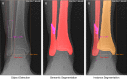

Purpose: Convolutional neural networks (CNNs) are increasingly being developed for automated fracture detection in orthopaedic trauma surgery. Studies to date, however, are limited to providing classification based on the entire image-and only produce heatmaps for approximate fracture localization instead of delineating exact fracture morphology. Therefore, we aimed to answer (1) what is the performance of a CNN that detects, classifies, localizes, and segments an ankle fracture, and (2) would this be externally valid?

Methods: The training set included 326 isolated fibula fractures and 423 non-fracture radiographs. The Detectron2 implementation of the Mask R-CNN was trained with labelled and annotated radiographs. The internal validation (or 'test set') and external validation sets consisted of 300 and 334 radiographs, respectively. Consensus agreement between three experienced fellowship-trained trauma surgeons was defined as the ground truth label. Diagnostic accuracy and area under the receiver operator characteristic curve (AUC) were used to assess classification performance. The Intersection over Union (IoU) was used to quantify accuracy of the segmentation predictions by the CNN, where a value of 0.5 is generally considered an adequate segmentation.

Results: The final CNN was able to classify fibula fractures according to four classes (Danis-Weber A, B, C and No Fracture) with AUC values ranging from 0.93 to 0.99. Diagnostic accuracy was 89% on the test set with average sensitivity of 89% and specificity of 96%. External validity was 89-90% accurate on a set of radiographs from a different hospital. Accuracies/AUCs observed were 100/0.99 for the 'No Fracture' class, 92/0.99 for 'Weber B', 88/0.93 for 'Weber C', and 76/0.97 for 'Weber A'. For the fracture bounding box prediction by the CNN, a mean IoU of 0.65 (SD ± 0.16) was observed. The fracture segmentation predictions by the CNN resulted in a mean IoU of 0.47 (SD ± 0.17).

Conclusions: This study presents a look into the 'black box' of CNNs and represents the first automated delineation (segmentation) of fracture lines on (ankle) radiographs. The AUC values presented in this paper indicate good discriminatory capability of the CNN and substantiate further study of CNNs in detecting and classifying ankle fractures.